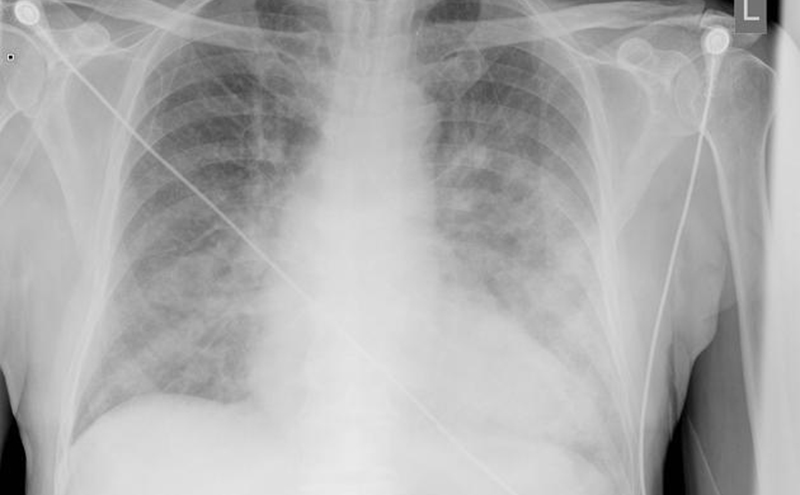

You place her on two liters of oxygen via nasal cannula, improving her oxygen saturation to 98%, and send her to the emergency department where a chest x-ray demonstrates bilateral increased bronchial wall visibility, central perihilar haziness, alveolar filling, and Kerley B lines consistent with mild pulmonary edema.

In terms of imaging, chest x-ray is a practical imaging modality to assess for SIPE. Radiographs may demonstrate signs of pulmonary edema such as cephalization of pulmonary vessels, loss of vascular definition, peribronchial cuffing, and Kerley B lines. Airspace opacities and pleural effusions may also be appreciated. It should be noted that there are cases of SIPE with a normal chest x-ray.4 Additional imaging modalities may include ultrasound or computed tomography (CT), which both are very sensitive in visualizing pulmonary edema or pleural effusions.4

Radiograph demonstrating pulmonary edema.

Radiograph courtesy of Dr. Jeremy Jones, Radiopaedia.org, rID-6463